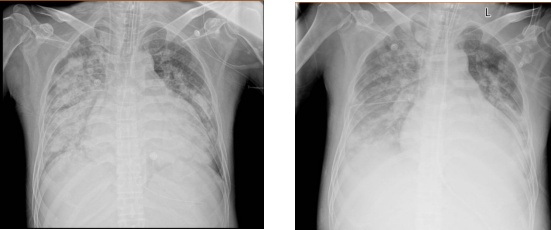

入院2天后,小刘的病情继续加重,不得不进行气管插管,转入ICU(重症医学科)治疗,随后胸片检查发现,小刘肺部出现了严重的“大白肺”症状。

刚入院1周的肺部影像

“大白肺”

是影像学中的一种通俗说法,是指肺部呈现白色的高密度影。

正常情况下,肺部由充满空气的肺泡组成,影像学检查时表现为黑色区域。当肺泡内出现炎症、感染、渗出液或炎性细胞时,射线无法穿透,影像学上就会出现白色区域,提示肺部存在严重的病变。